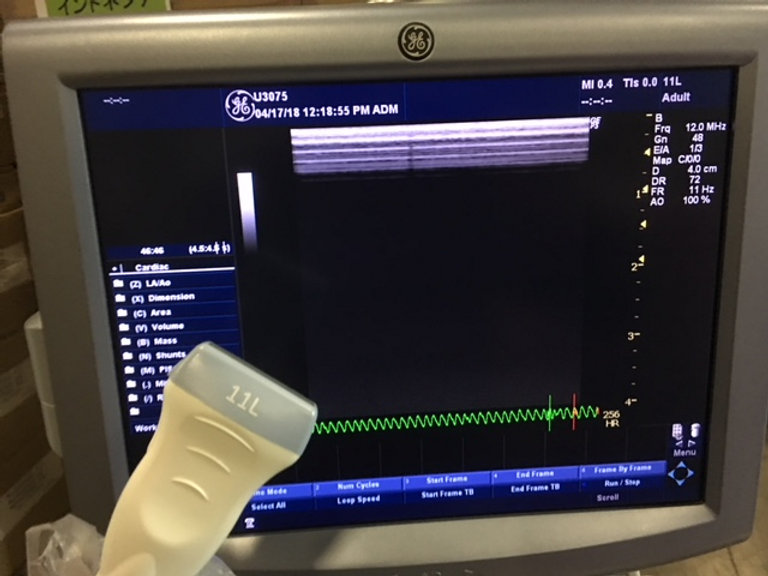

GE Logiq P5 d’occasion Lieu : Australie (U3075) Fabriqué : Oct 2013 Version du logiciel : R4.0.6 Options installées : Basic, Anatomical M, Cross Beam, SRI, Auto Sondes IMT : 5Sp, 8C, 11L